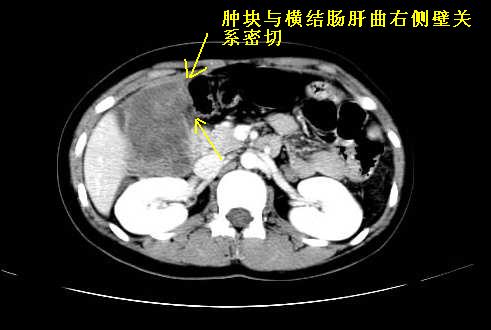

我坚决反对您的观点,该病例定位:横结肠肝曲与升结肠之间的肠系膜及部分肠壁。请看下图:

病灶巨大,少部分向肠腔内生长,大部分向长腔外生长。其密度不均匀,增强显示明显不均匀强化,并见有大片状始终不强化的不规则坏死液化区。虽然病灶中上部形态尚可,病人又如此年轻,但中下部形态、密度、强化特点强烈提示为恶性病灶。综上,我考虑本病例为:恶性胃肠道间质瘤。